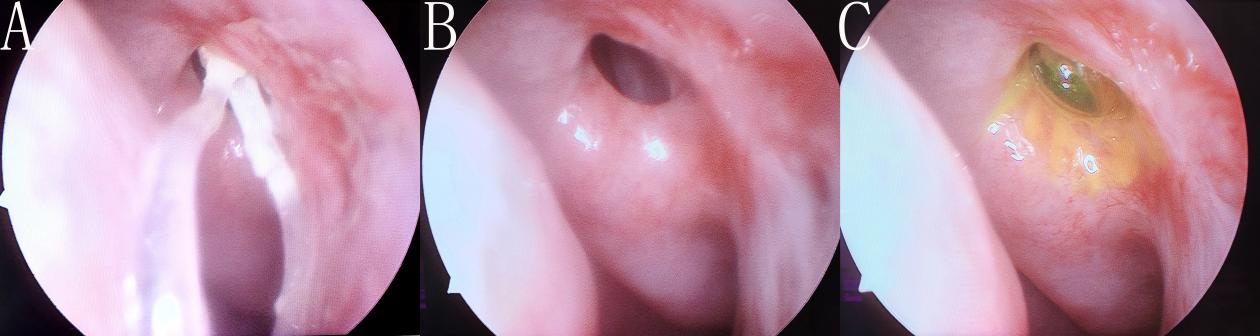

图3 一例手术成功患者术后鼻内镜检查结果

Figure 3 Endoscopy examination of a success patient

本研究共纳入69例患者(69只眼),其中5例患者未能完成术后9个月随访而未纳入。2例术中通过直径3 mm的剥离子对比核对不符合小泪囊诊断而未纳入,1例患者在术后1个月人工泪管脱出而未纳入。最终纳入61例患者,平均年龄为(55.31±12.28)岁(范围为27~75岁)。其中女性40例,男性21例,右眼33眼,左眼28眼。CT-DCG显示纳入患者的泪囊三维情况:泪囊水平径为(2.58±0.34)mm、前后径为(2.55±0.31)mm、垂直径为(4.43±0.66)mm。所有患者均顺利完成开放泪总管平面的En-DCR联合BSTI术治疗。人工泪管于术后3个月在门诊内镜室取出。经过9个月系统随访,基于既定成功率评定标准,本研究的解剖成功率为80.33%(49/61)(表1),其中3例存在泪溢症状(MUNK 3级2例、4级1例),故功能成功率为75.41%(46/61)(图3)。在解剖性失败的12眼中,11眼归因于吻合口闭锁(瘢痕性闭锁9眼,肉芽增生闭锁2眼),另外1眼系泪总管阻塞所致。术中并发症包括:2例上颌骨额突骨创面渗血(肾上腺素棉片压迫无效,改行骨蜡封闭止血);1例鼻黏膜动脉性出血(双极电凝止血)。在整个术后随访过程中,无需要填塞的鼻腔出血、术后感染、术后视物重影和视力下降等并发症发生。在术后3个月内人工泪管在位患者的随访过程中,3例患者(4.92%,3/61)发现吻合口处的肉芽增生,门诊内镜室用带吸引的剥离子进行肉芽切除,之后随访未见肉芽复发。

尽管手术过程和术后用药、随访处理做了相应改良,泪囊鼻腔吻合口由于肉芽组织和瘢痕组织增生引起的闭锁仍是En-DCR手术失败的主要原因,这与既往的研究报道相一致[3-6, 15, 24-25]。通过术后9个月的系统随访,基于既定的评判标准,80.33%(49/61)的患者取得了解剖性成功,其中3眼存在溢泪症状(MUNK 3级2例、4级1例),故功能成功率为75.41%(46/61)。在解剖性失败的12眼中,11眼归因于吻合口闭锁(瘢痕性闭锁9眼,肉芽增生闭锁2眼),另外1眼系泪总管阻塞所致。